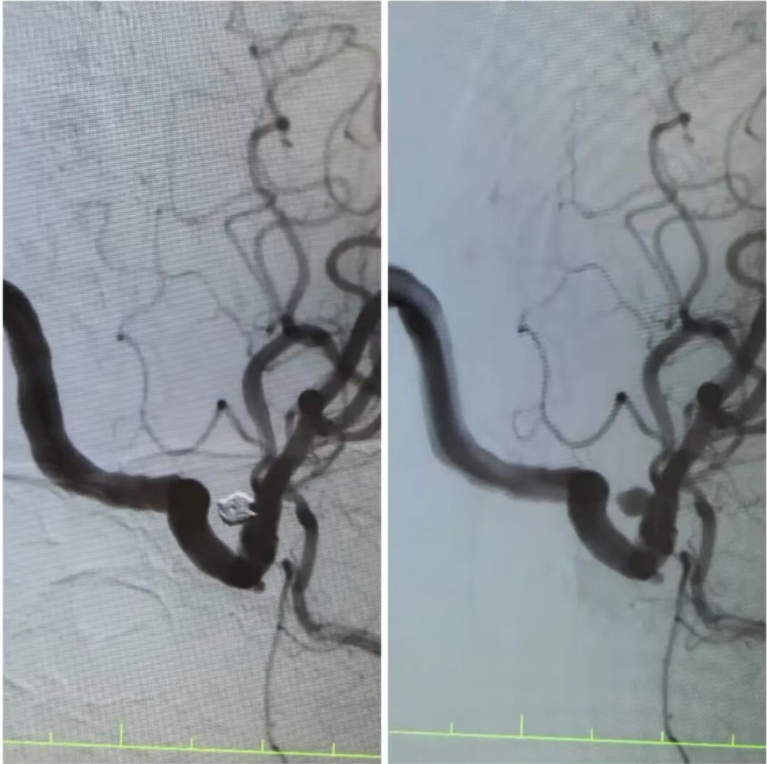

在王阿姨的造影檢查上,可清晰地看到動(dòng)脈瘤的形態(tài):如同血管上懸掛的“小囊袋”,薄如蟬翼的瘤壁隨時(shí)可能再次破裂?!伴_(kāi)顱手術(shù)創(chuàng)傷大,老人基礎(chǔ)疾病多,風(fēng)險(xiǎn)極高,而介入栓塞術(shù),能通過(guò)股動(dòng)脈穿刺的“鑰匙孔”路徑,精準(zhǔn)封堵動(dòng)脈瘤?!笔中g(shù)團(tuán)隊(duì)反復(fù)推演方案,最終選定顱內(nèi)動(dòng)脈瘤栓塞術(shù)——用纖細(xì)的微導(dǎo)管將彈簧圈送入動(dòng)脈瘤腔內(nèi),像“織網(wǎng)”一樣填充瘤腔,隔絕血流沖擊,從根源上消除破裂風(fēng)險(xiǎn)。

手術(shù)臺(tái)上,丁院長(zhǎng)握著導(dǎo)管在血管中精準(zhǔn)穿梭,如同在迷宮中尋找唯一的出口。當(dāng)微彈簧圈依次填入動(dòng)脈瘤,造影顯示瘤腔被完美“封堵”,載瘤動(dòng)脈血流恢復(fù)通暢,這枚困擾老人許久的“炸彈”,終于被安全拆除。術(shù)后的王阿姨頭暈頭痛癥狀消失,胸悶氣短的老毛病也因身心狀態(tài)改善而減輕?!案杏X(jué)腦袋里的‘炸彈’沒(méi)了,整個(gè)人都輕快了!”